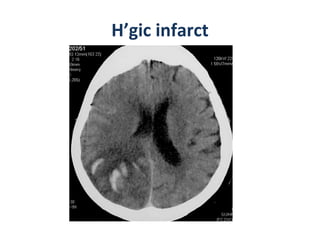

CT – sub acute infarct PLAIN CT Wedge-shaped  area of decreased attenuation involving  gray/white matter  in  typical vascular distribution Mass effect initially increases, then begins to diminish by 7-10 days  H’gic transformation  occurs in 15-20% of MCA occlusions, usually by 48-72 hrs CECT Enhancement patterns typically  patchy May appear as early as 2-3 days , persisting up to 8-10 weeks &quot;2-2-2&quot; rule  = enhancement begins at 2 days, peaks at 2 weeks, disappears by 2 months

H’gic infarct

CT – subacute infarct PLAIN CT Wedge-shaped area of decreased attenuation involving gray/white matter in typical vascular distribution Mass effect initially increases, then begins to diminish by 7-10 days H’gic transformation occurs in 15-20% of MCA occlusions, usually by 48-72 hrs CECT Enhancement patterns typically patchy May appear as early as 2-3 days , persisting up to 8-10 weeks &quot;2-2-2&quot; rule = enhancement begins at 2 days, peaks at 2 weeks, disappears by 2 months